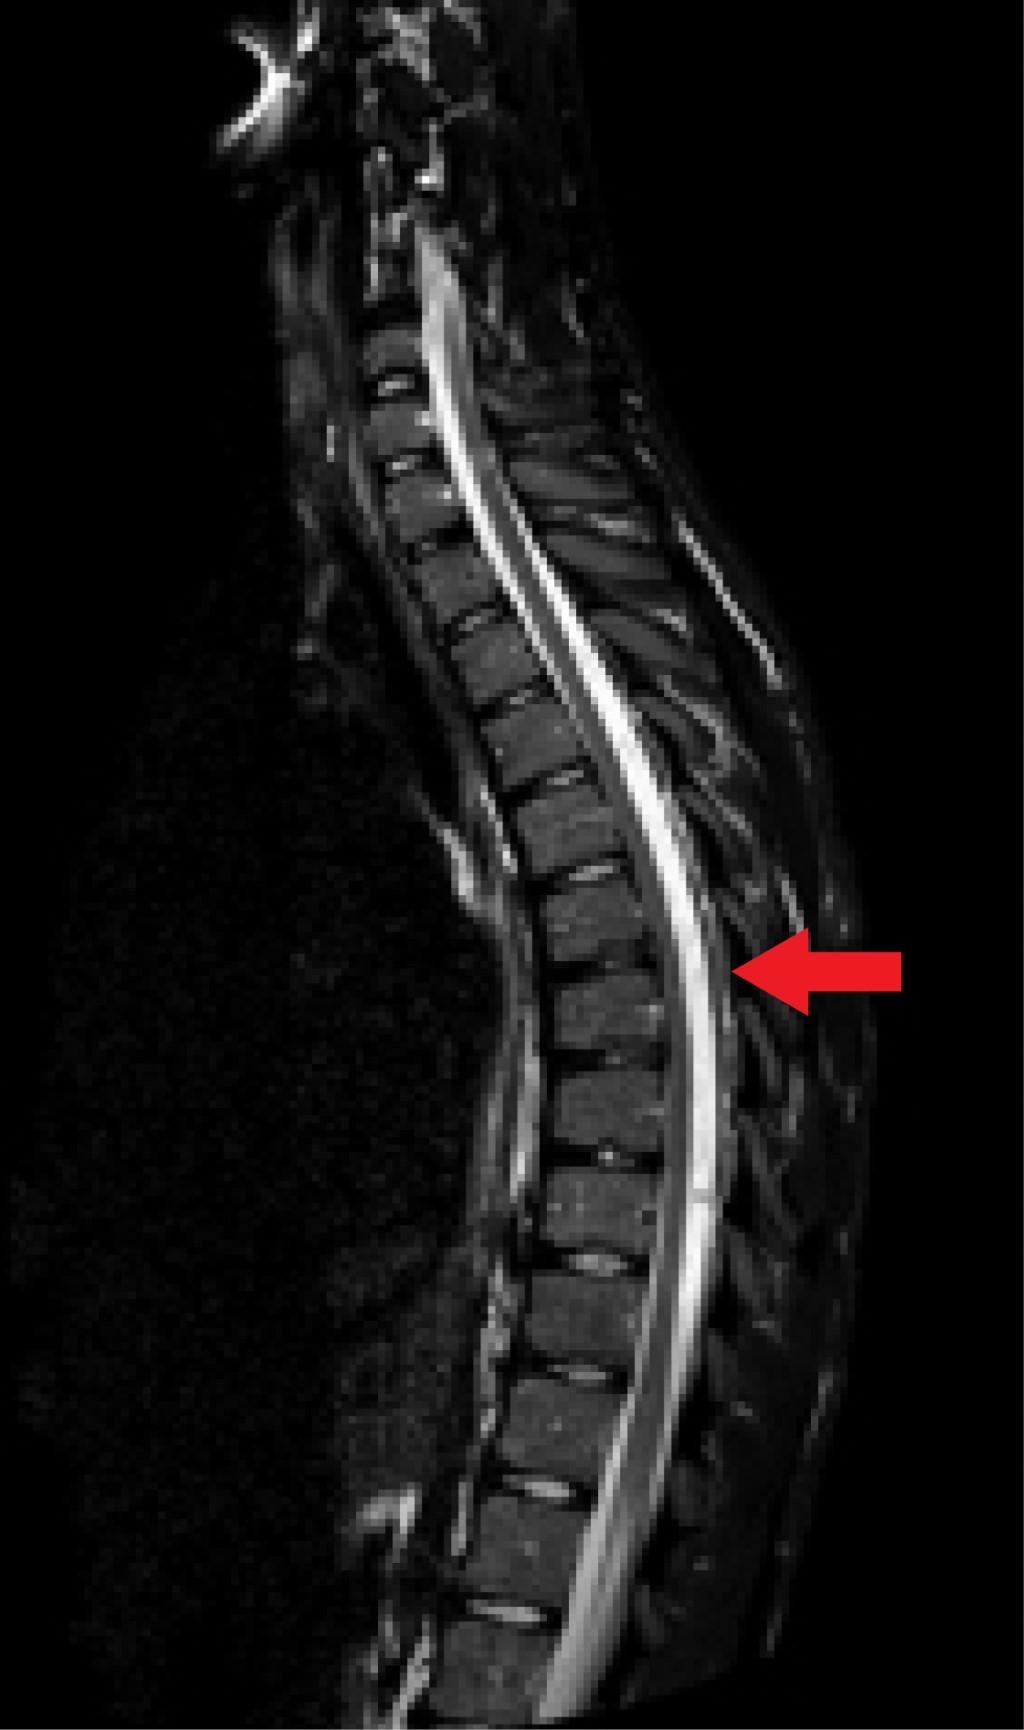

La RM (realizada 20 días después de la segunda consulta) muestra un material hipertenso en las secuencias T1 (Figura 1) y T2 (Figura 2) e hipointenso en la secuencia STIR (Figura 3) en el espacio epidural posterior desde D3 a D9. Con ello se llega al diagnóstico de lipomatosis espinal epidural posterior desde D3 a D9.

El estándar de oro para el diagnóstico de la SEL es la RM ponderada en T1 y las imágenes axiales y sagitales pueden mostrar un aumento de la grasa epidural como una imagen hiperintensa. Las imágenes ponderadas en T2 muestran una intensidad intermedia; la supresión grasa (STIR) es el método de diagnóstico definitivo, mostrando la SEL como una imagen hipointensa.13

Figura 3